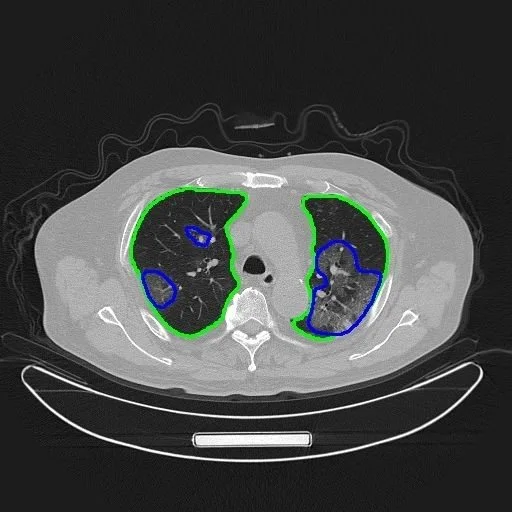

https://p6-tt.byteimg.com/origin/pgc-image/ShBXyTB6JVGrDc?from=pc这种风气甚至被一些学者利用,来“忽悠”审稿人,“比如,为了体现论文的创新性,他们会在论文中写一些创新点,而在他们的算法实现中并没有都用到它们,或者起的实质作用并不大,实际上主要还是靠现有的深度学习方法或者加上一些小的implementation trick。另外,以图像分割的论文为例,有人在论文中不仅采用了深度学习,也用了传统方法对深度学习分割结果做了后处理,有时还能够显著改进深度学习直接得到的分割结果;但为了迎合做深度学习的审稿人,他们可能会轻描淡写甚至不提传统方法的作用,而是突出在深度学习框架里的创新点所起的作用。这几种文章发表以后,作者通常也不愿意公开所有的源代码。”

例如,医疗AI的训练数据,简单的“拷贝”并不能满足模型训练的需要,只有让医生耗费精力标注、分割才能在在模型上使用,这会耗费很大的成本,学术界很难做到。